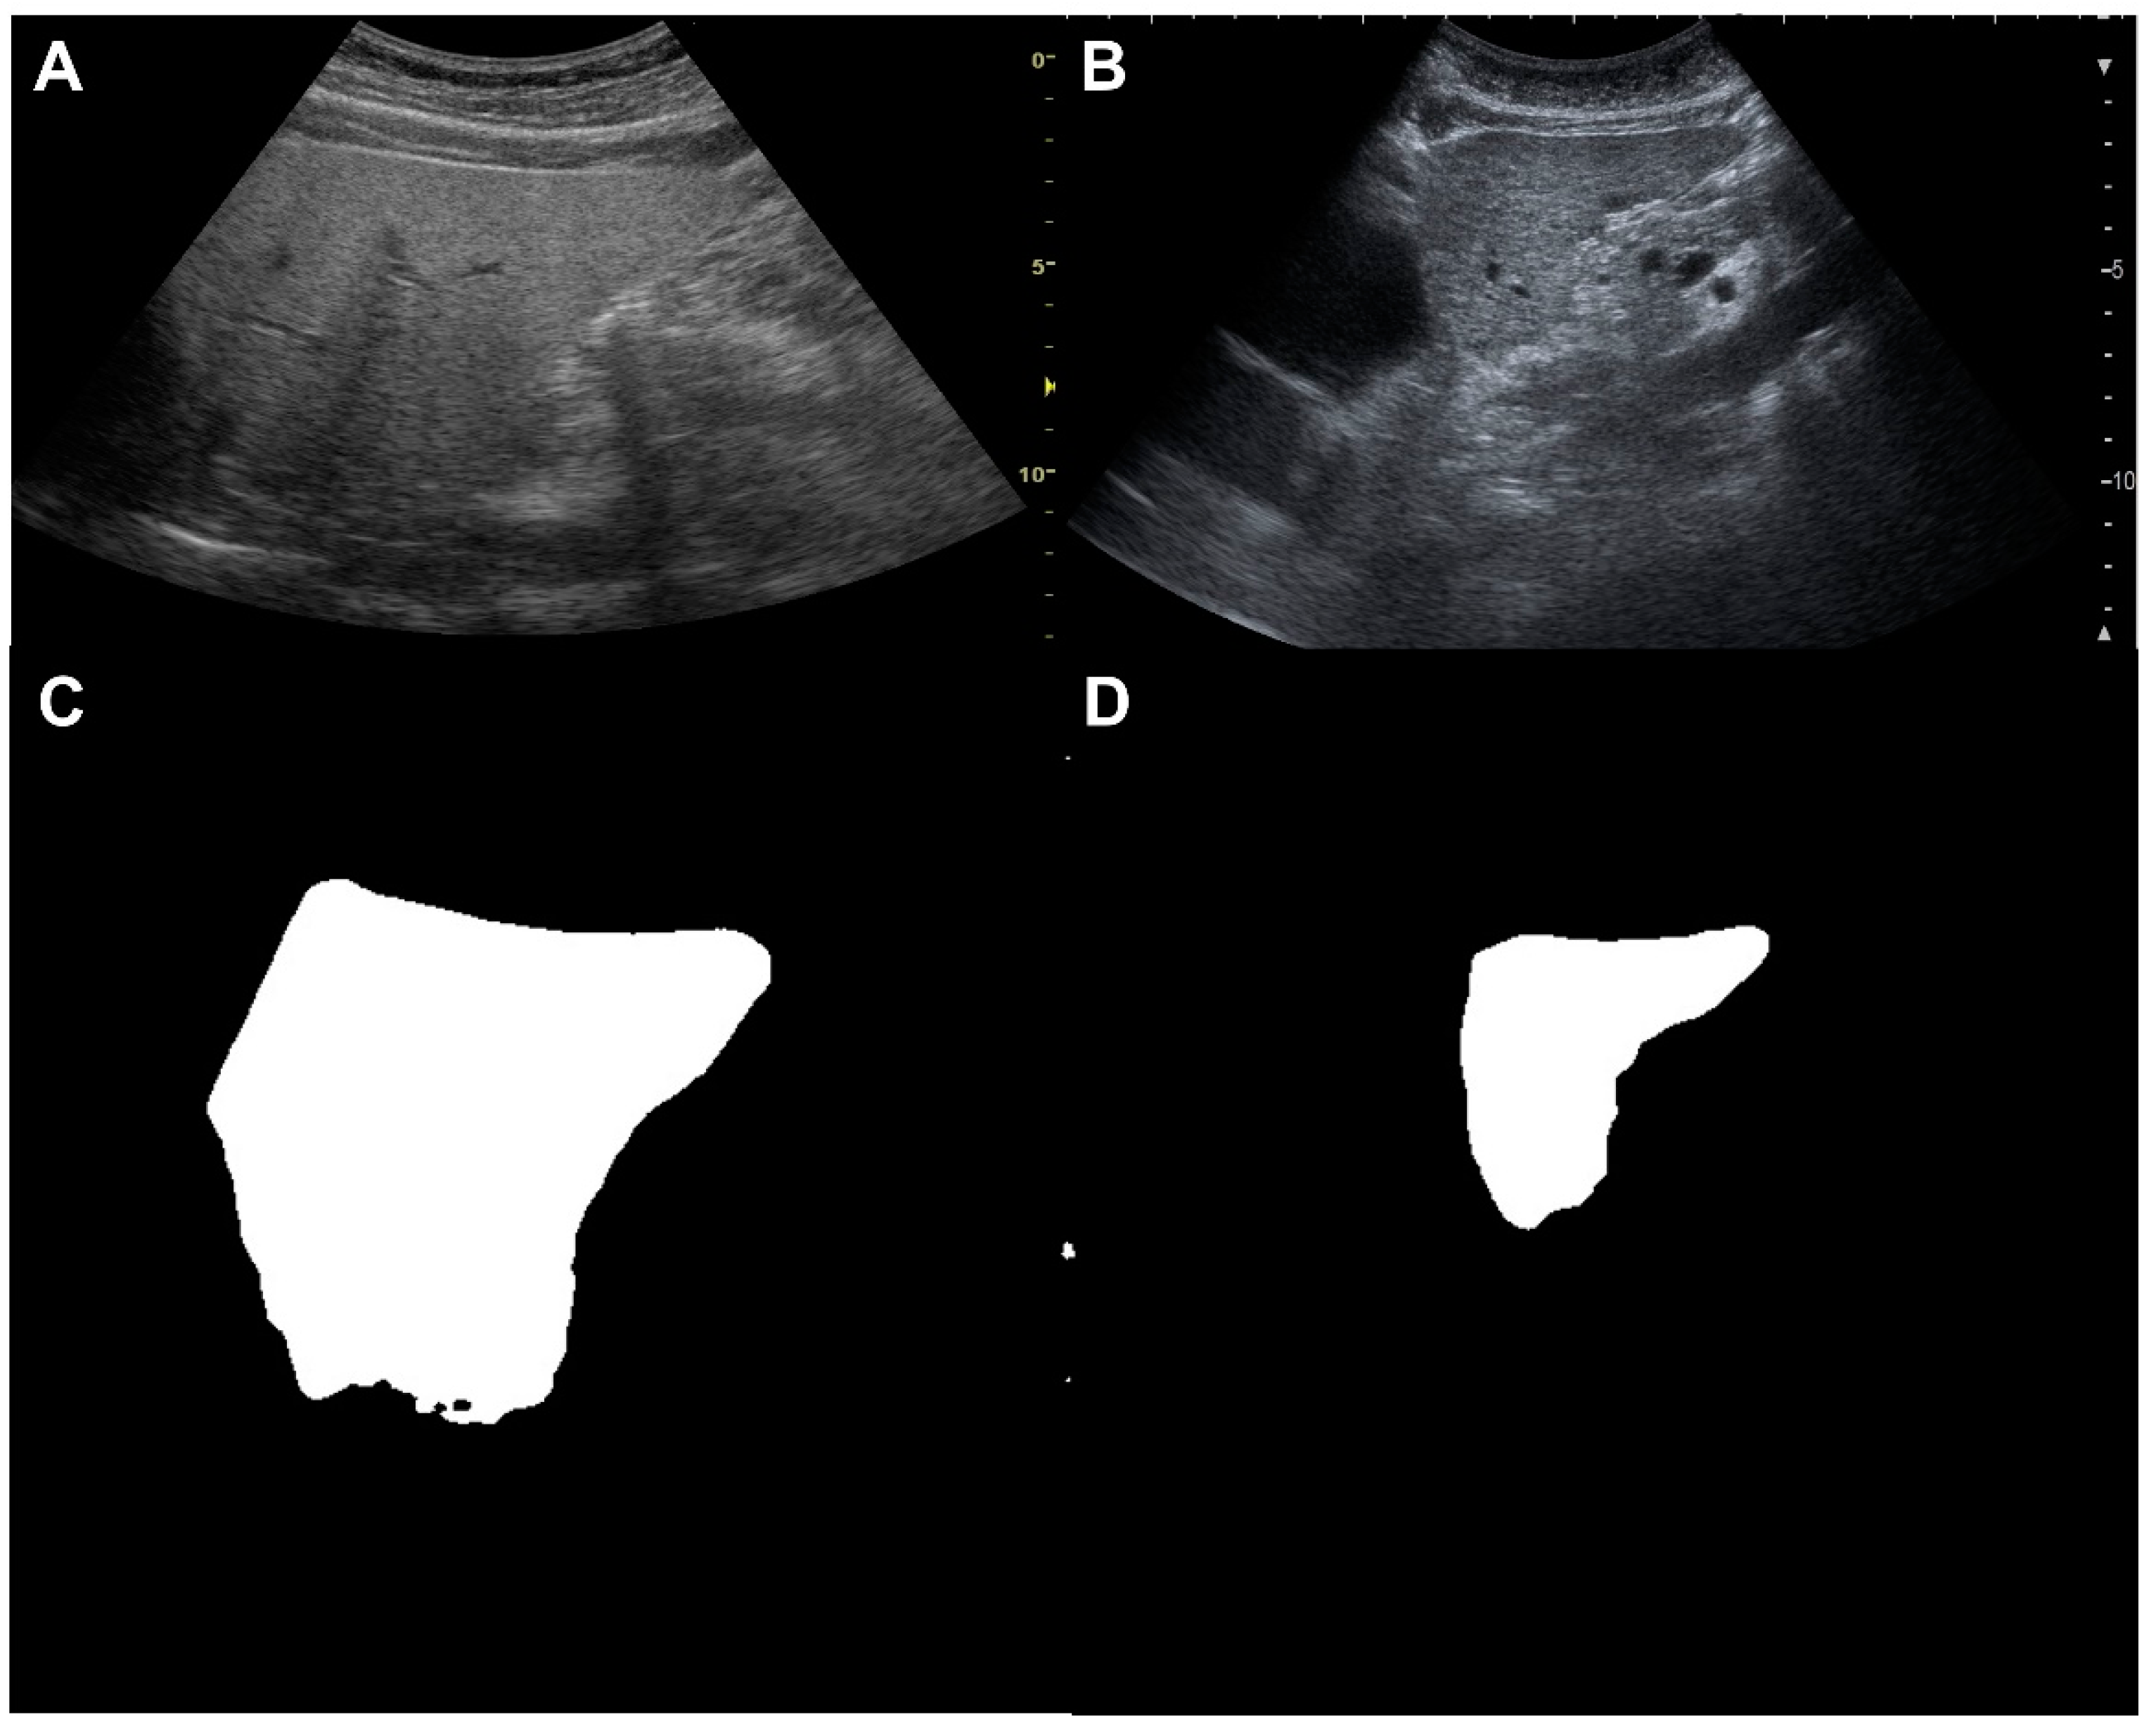

2.5. Image Pre-Processing and Classification of the Liver Surface Roughness via Deep Learning

3.2. Results of the Classification of the Liver Surface Roughness via Deep Learning